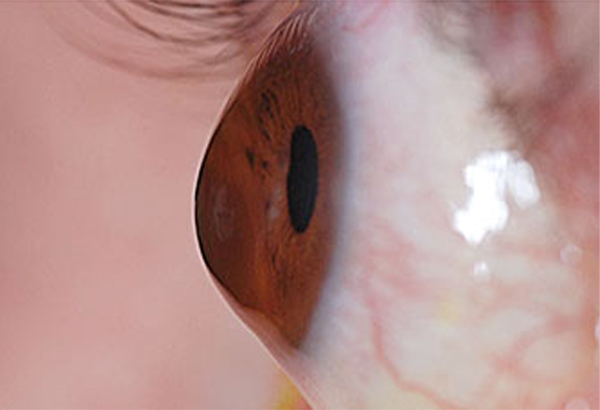

원인 : 각막이 일부가 얇아지면서 원래 모양을 유지 못하고 돌출되는 진행성 질환이며 각막두께를 안전 기준 이하로 수술받을 경우, 눈을 자주 비비는 행동 등 충격이 자주 가해졌을 때 원추각막이 발생합니다.

CASE1_축농증 수술 후 심한 눈비빔 습관, 원추각막 진단받은 사례

CASE2_원추각막 진단받은 사례